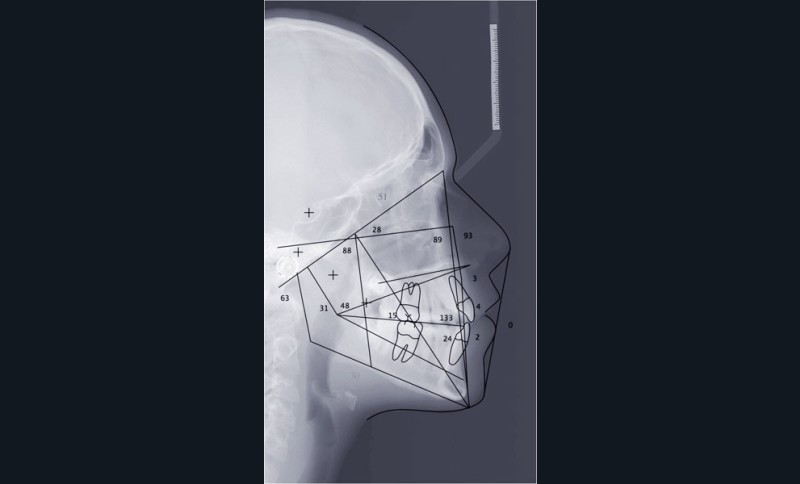

Le cas d’Anthony âgé de 11 ans et 7 mois qui présente une endomaxillie bilatérale associée à un léger encombrement mandibulaire dans un contexte de classe I squelettique hyperdivergente (fig. 1 à 10) est très représentatif de ce que peuvent apporter les forces légères appliquées aux alvéoles dentaires tout en intégrant des torques spécifiques qui permettent de contrôler parfaitement l’orientation radiculaire (fig. 11 à 29).